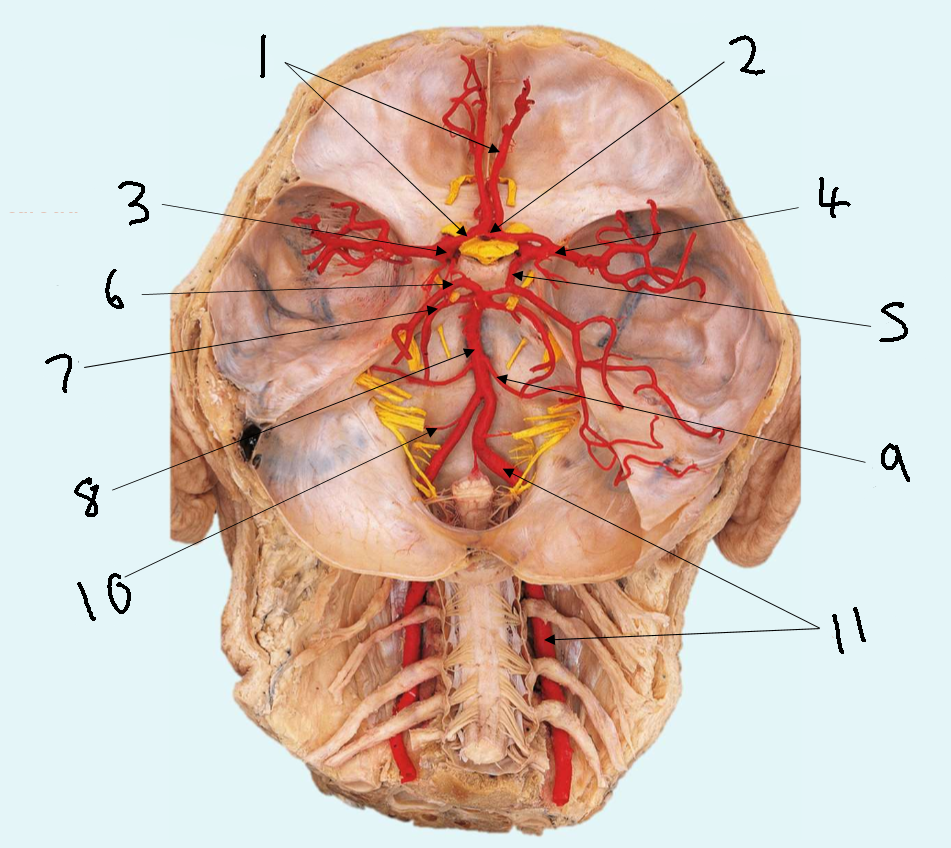

What is 1?

anterior communicating artery

What is 2?

anterior cerebral artery

What is 3?

middle cerebral artery

What is 4?

internal carotid artery

What is 5?

posterior communicating artery

What is 6?

posterior cerebral artery

What is 7?

superior cerebellar artery

What is 8?

pontine arteries

What is 9?

basilar artery

What is 10?

anterior inferior cerebellar artery

What is 11?

vertebral artery

What is 12?

posterior inferior cerebellar artery